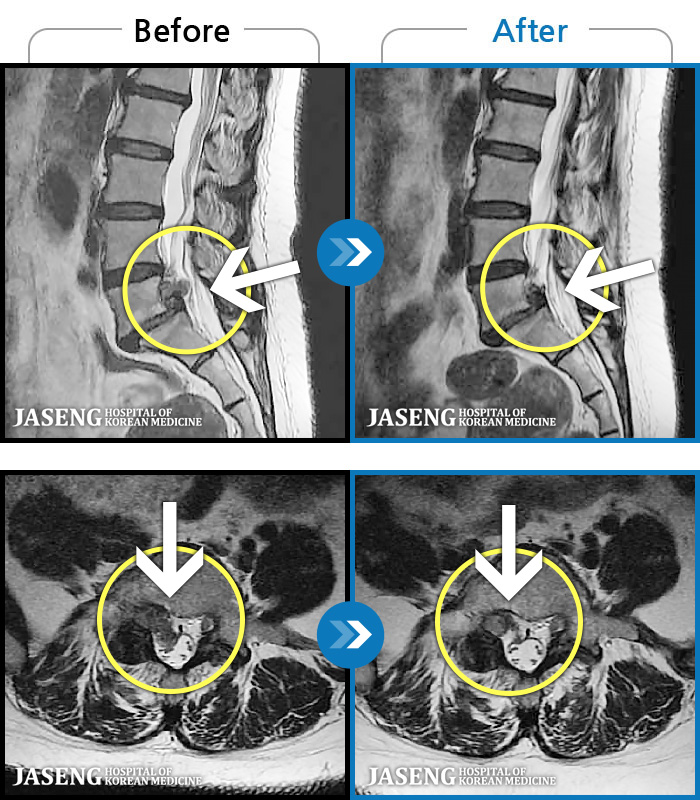

Before

After

환자에게 사전 동의를 받아 동일 조건에서 촬영되었습니다.

개인에 따라 치료 후 부작용이 발생할 수 있으니 의료진과 상담 후 치료를 진행하시기 바랍니다.